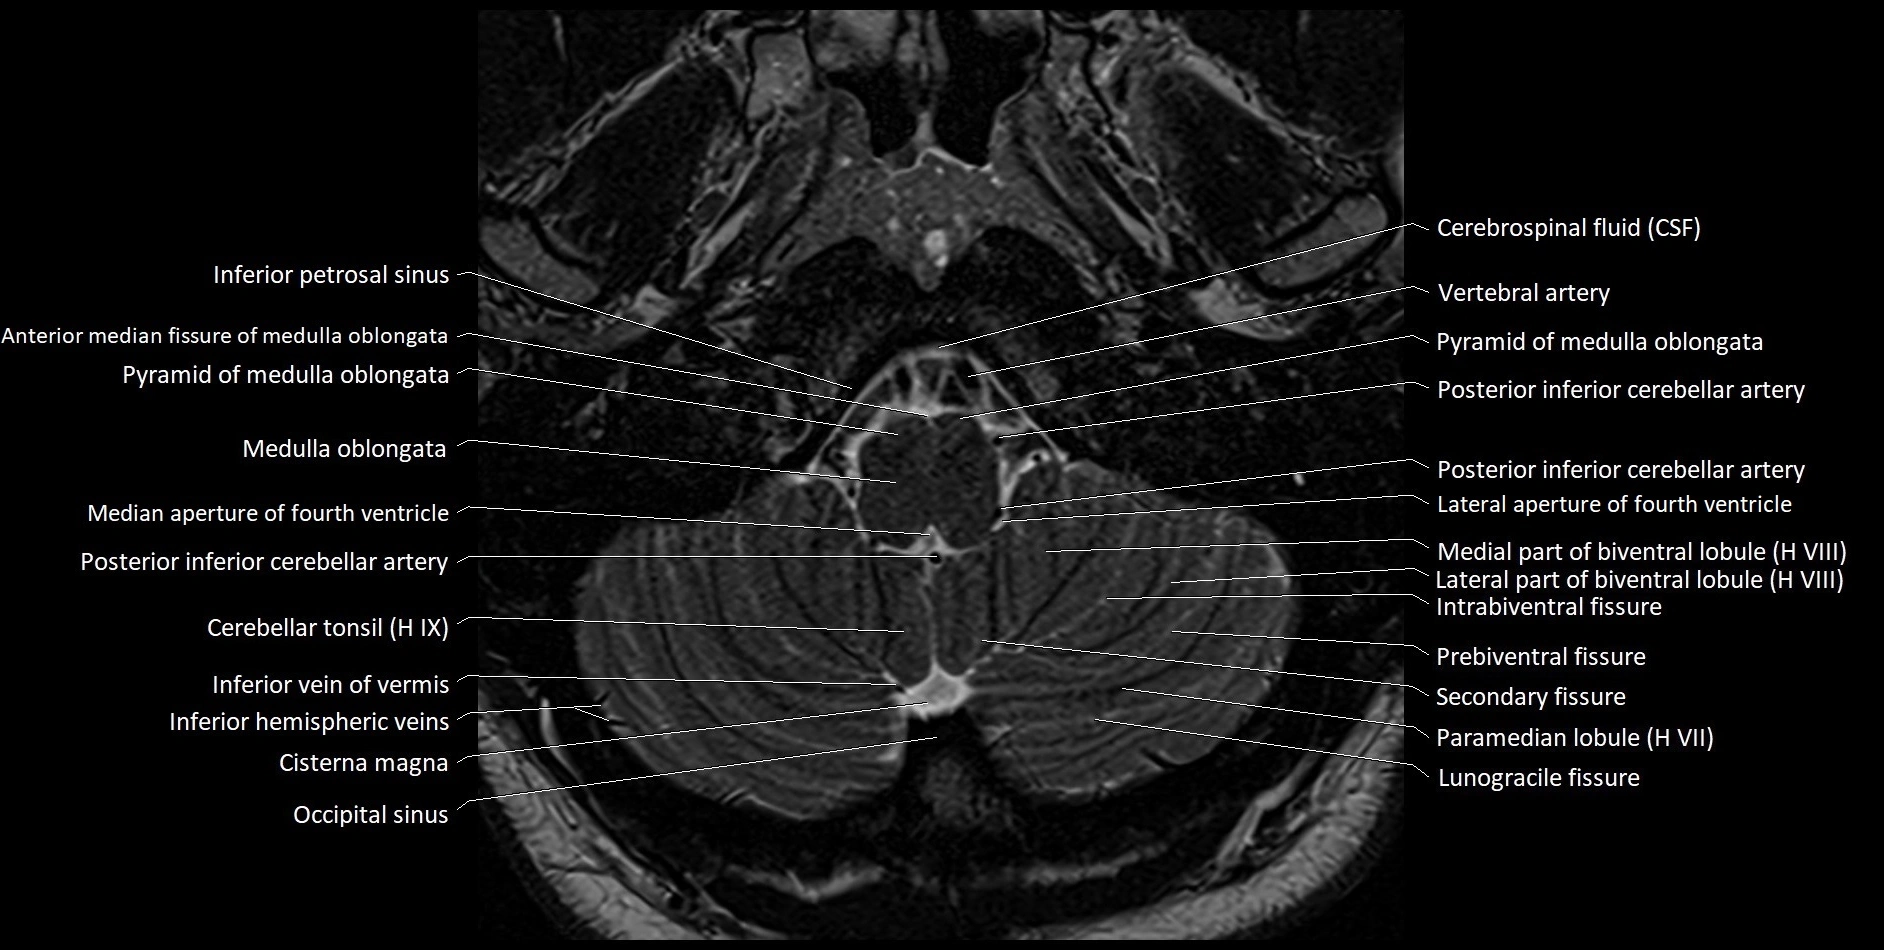

Experience the next generation of cross-sectional anatomy with our advanced 3T MRI, enhanced by AI-powered Deep Resolve reconstruction. Our ultra-high-resolution imaging (0.3–0.7 mm in-plane resolution) combined with ultra-small field-of-view techniques reveals fine anatomical detail with exceptional clarity, redefining anatomical visualization and education.

Explore an advanced library of ultra-high-resolution MRI anatomy, developed from hundreds of repeated scans of volunteers using cutting-edge 3T scanners, dedicated coils, and AI-powered enhancement. These images capture real anatomical detail, revealing even the smallest microstructures while preserving the authenticity of true clinical imaging without over-reliance on virtual labeling.

All our cross-sectional images are meticulously hand-labeled by professionals with over 20 years of experience in cross-sectional imaging. This is the result of over six years of dedicated work, precision, and passion. Every image is individually checked and verified by senior consultant radiologists from major London NHS trusts, each with relevant subspecialty expertise—ensuring the highest level of accuracy and clinical relevance.